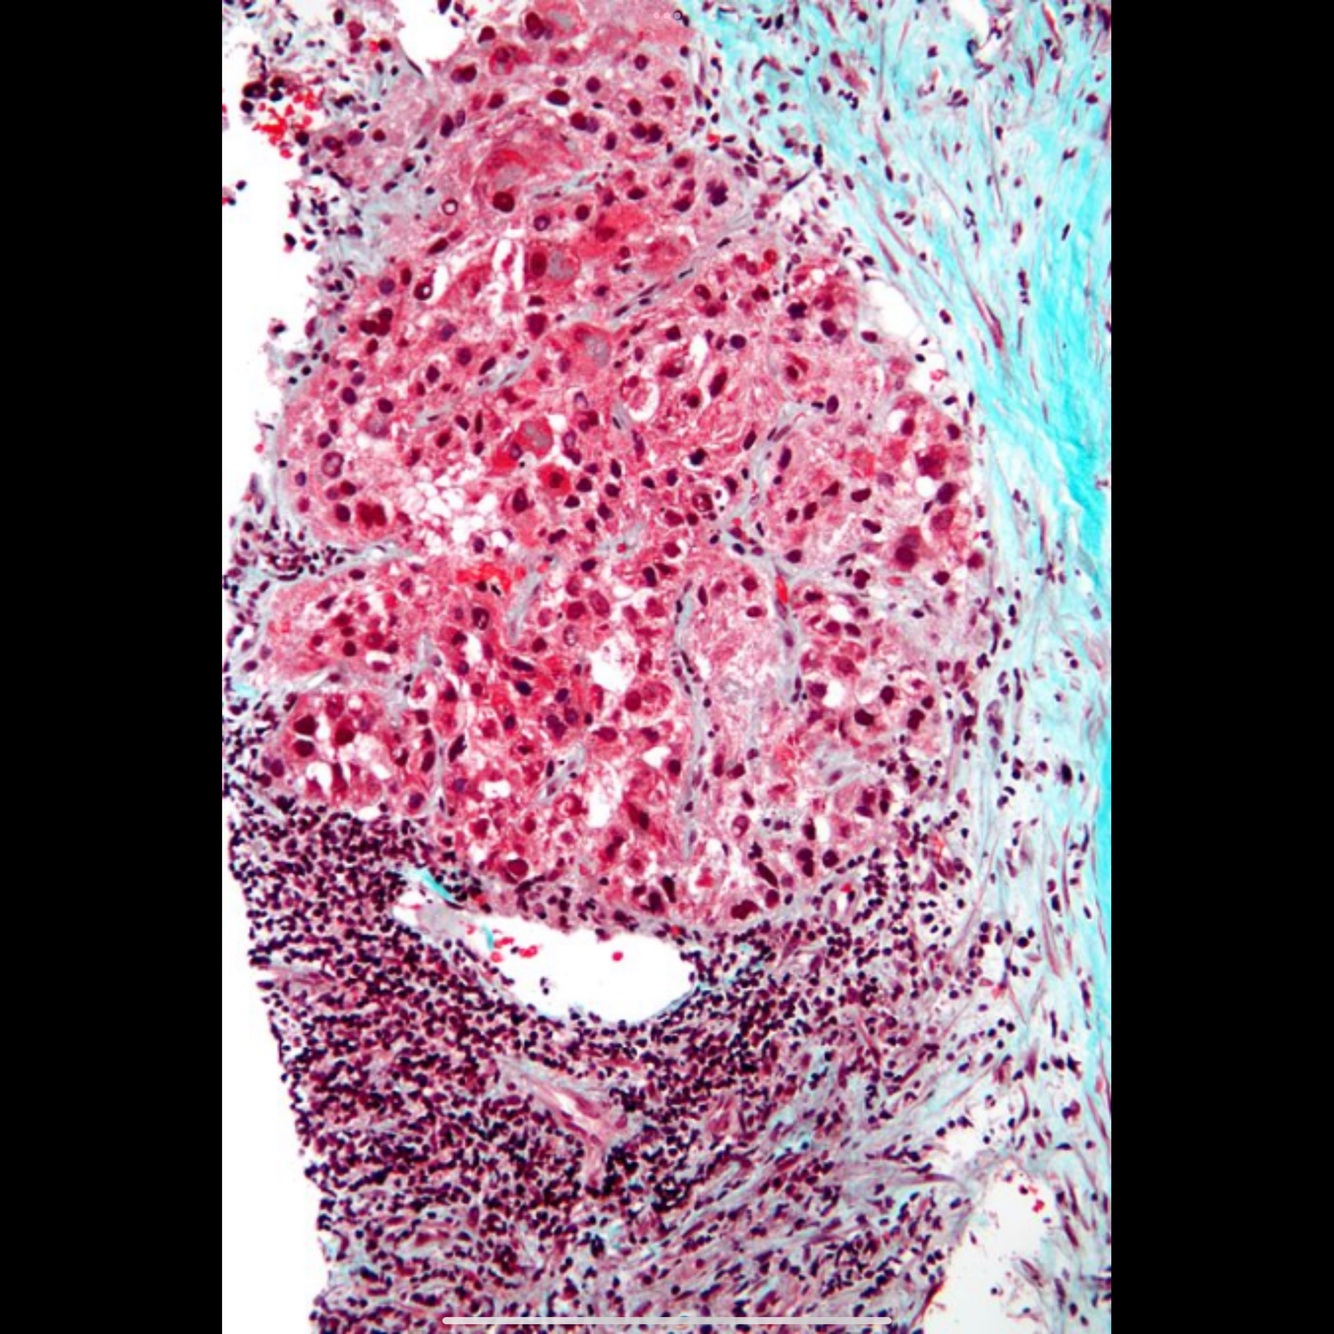

Cirrhosis is characterized pathologically by regenerative nodules with thick, collagenous septae.